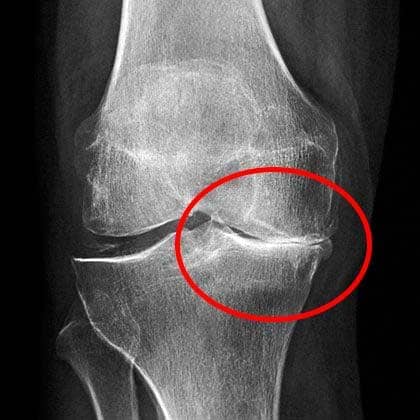

Ese fue un punto de quiebre aterrador. Si le decía a mi jefe que no podía cargar nada, seguramente me despedirían. Las radiografías mostraban un serio desgaste en las articulaciones.

Las radiografías mostraban un serio desgaste en las articulaciones.